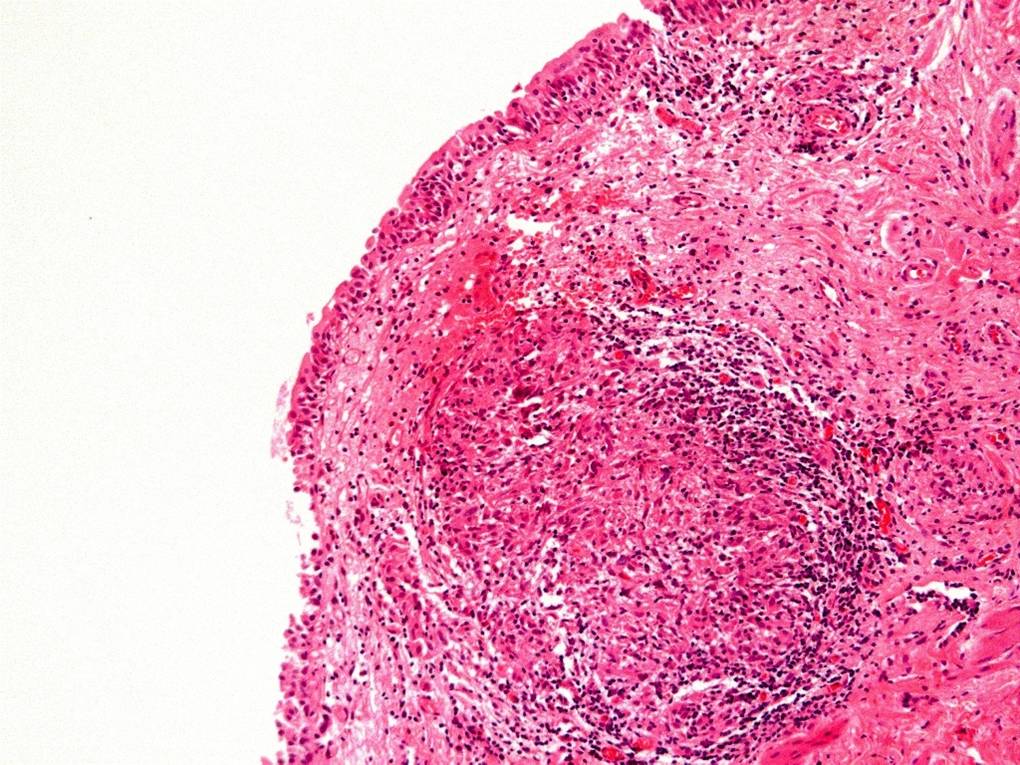

Bladder Flat Lesions

Case ID: 80